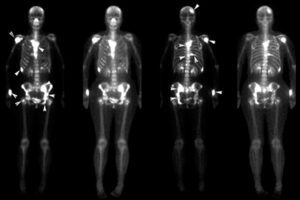

آزمایشهای سرطان استخوان در اینجا بر روی سرطانهای اولیه استخوان (سرطانهایی که در استخوانها شروع میشوند) تمرکز میکنند که اغلب در بزرگسالان دیده میشود. اطلاعات